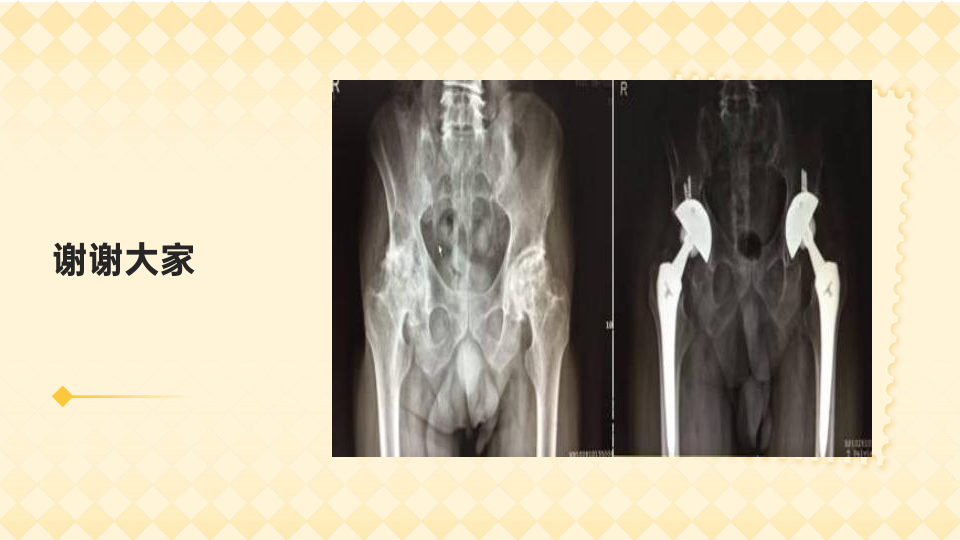

股骨头坏死的预防与治疗